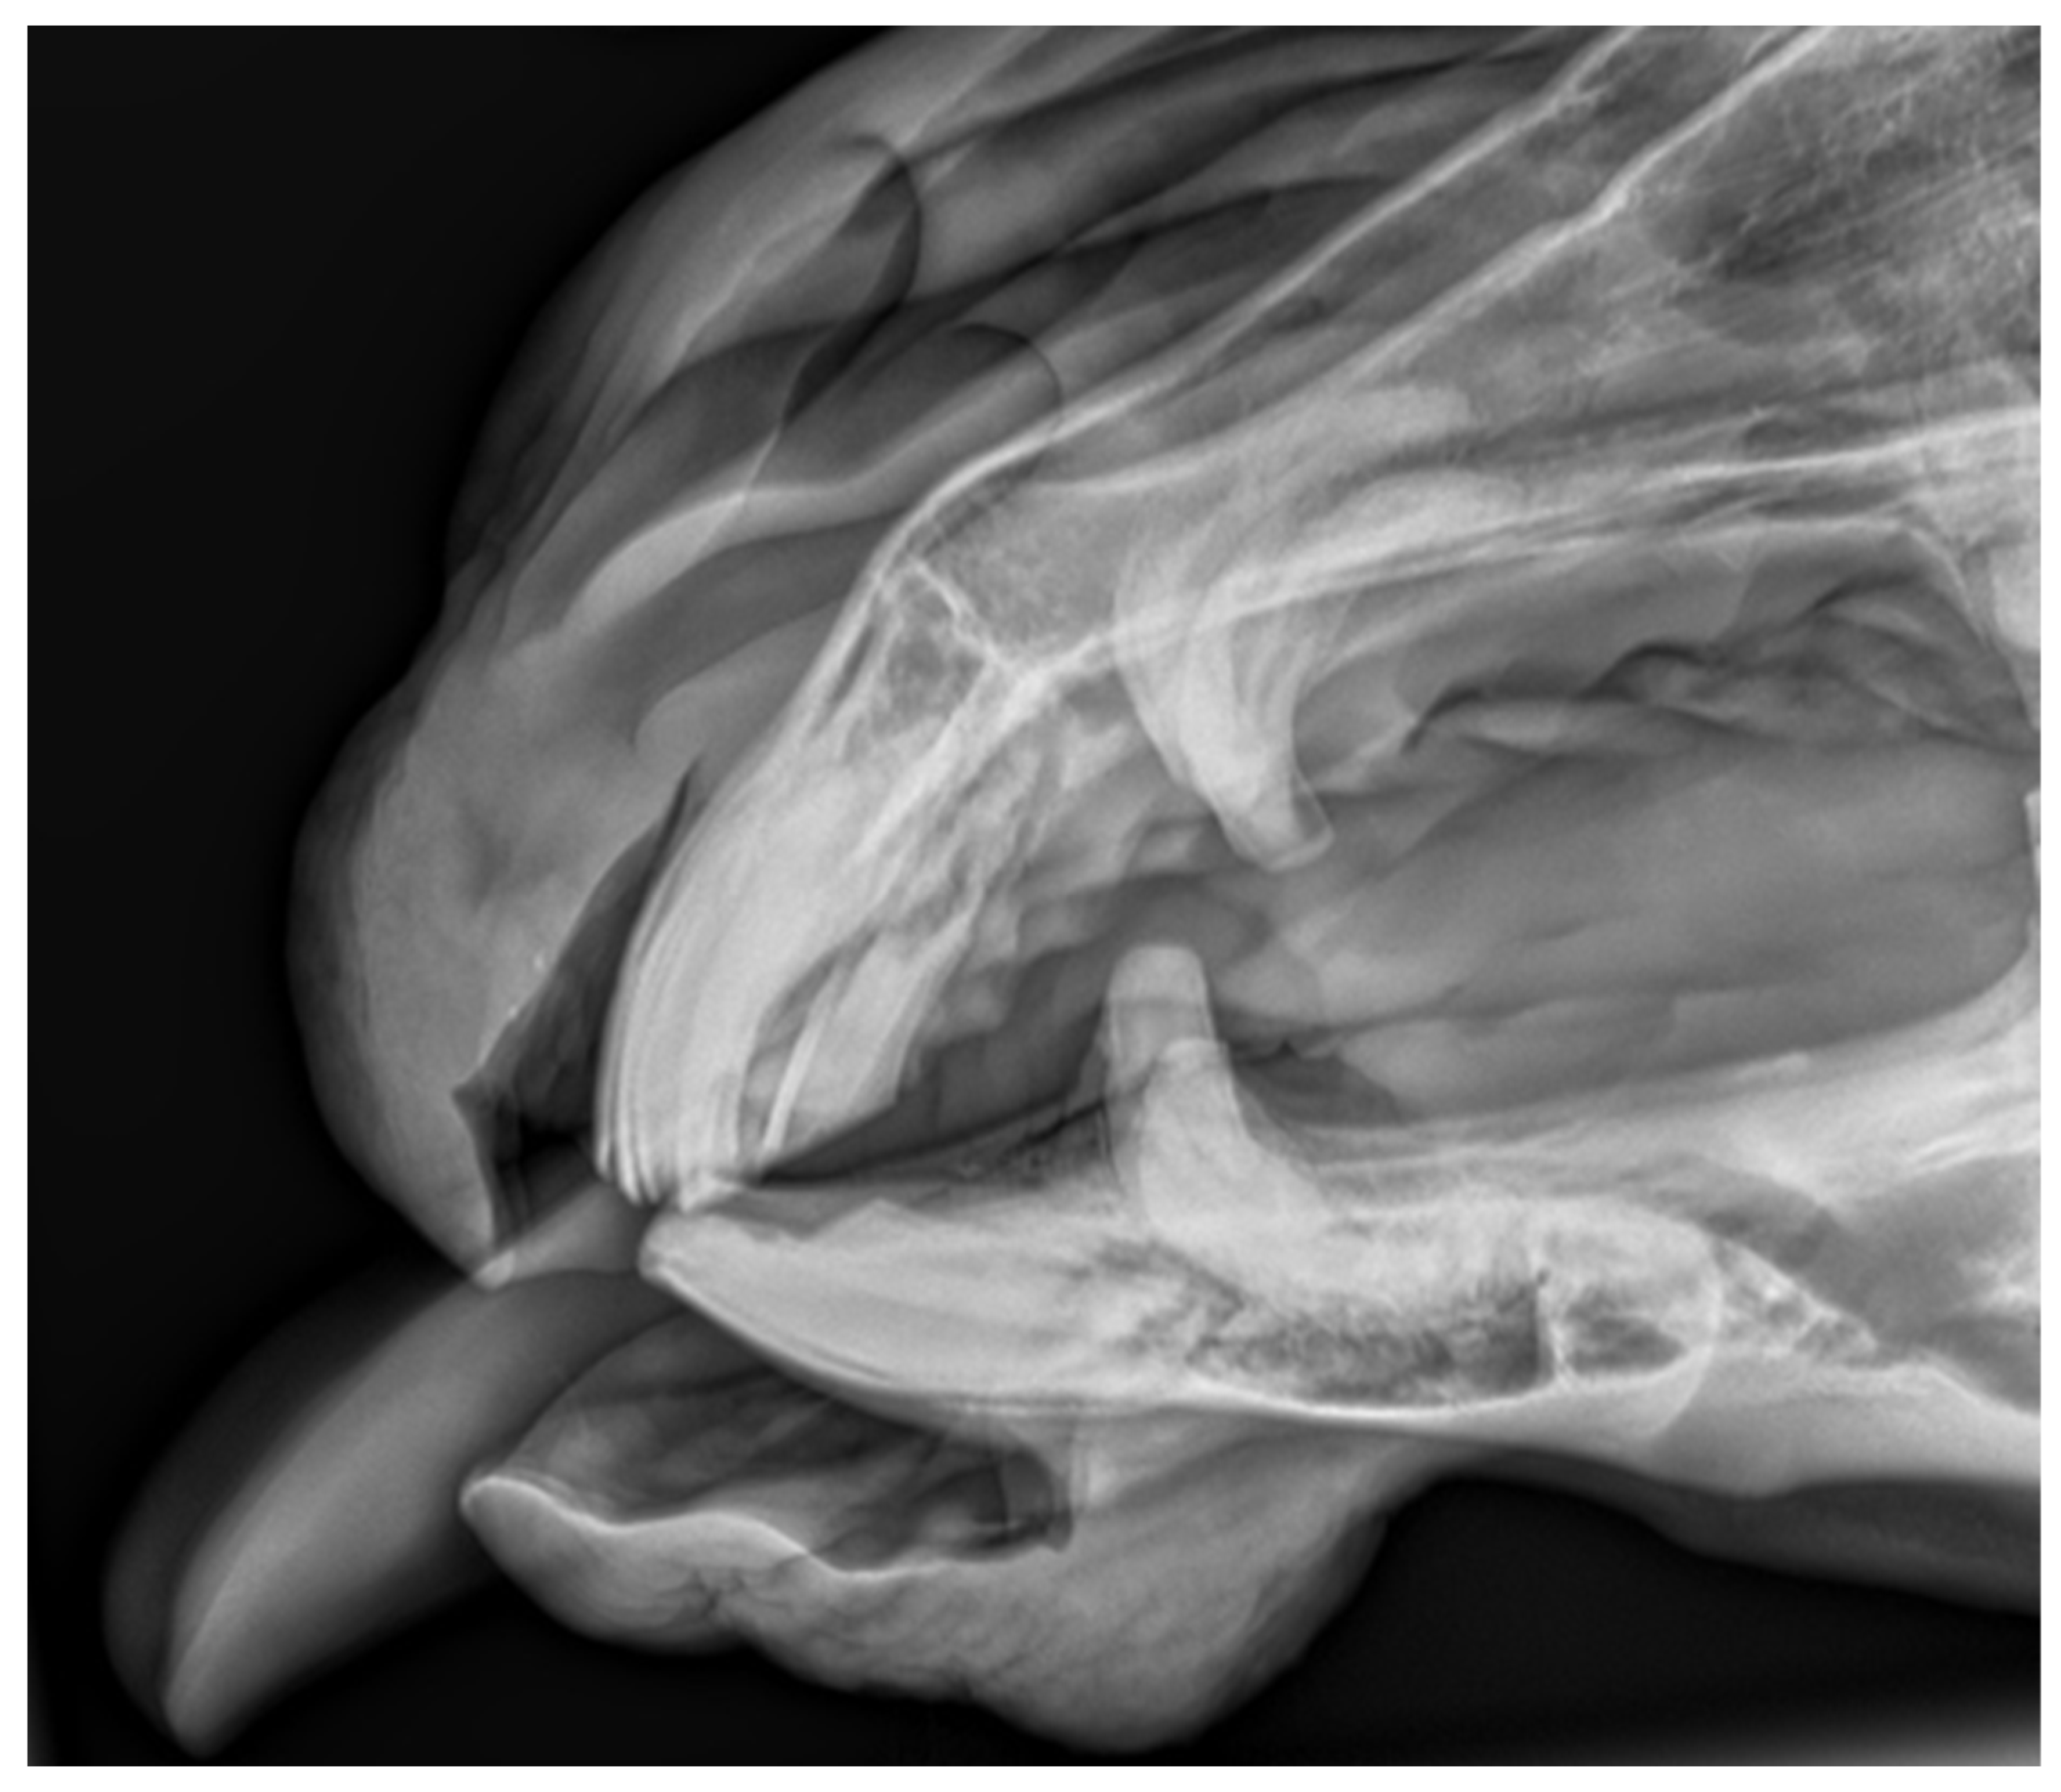

2.1.1. Case 1

2.1.2. Case 2